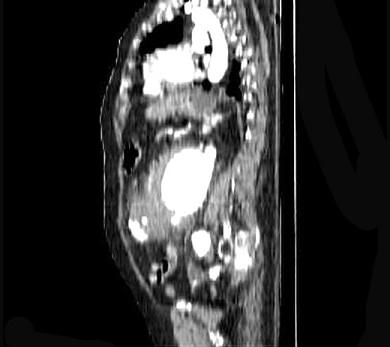

问题 关于腹主动脉瘤,下列哪项是正确的 ( )

选项 A、外科手术是根治腹主动脉瘤的唯一方法 B、CT能够更准确地显示瘤体的三维形态体征 C、腹主动脉瘤病人出现腹痛或腰背痛时意味着动脉瘤破裂 D、MRI在造影剂的帮助下可以充分显示瘤体的大小 E、直径2cm以上的动脉瘤可以用超声多普勒检查出来

答案 C